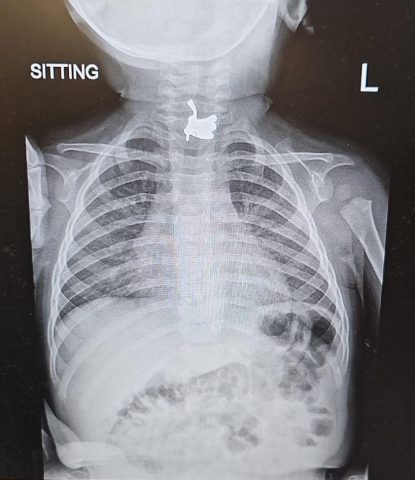

איילת שלז, סגנית מנהל המחלקה לרפואה דחופה ילדים במרכז רפואי מאיר מספרת: "מיד עם קבלתו במיון ילדים ולאחר תיאור המקרה של הורי התינוק החשד שלנו אכן היה שהוא בלע גוף זר ועל אף כי לא נצפה דבר בלוע, העברנו אותו לצילום שאישש כי ישנו גוף זר בחלק העליון של הוושט. יצרנו קשר עם מחלקת אף אוזן גרון והוא הועבר באופן מיידי לחדר הניתוח".

המגנט הוא בצורת ינשוף וכאשר הוא נשבר הפעוט בלע חלק ממנו בצורת נוצות שהתיישב בוושט. במרכז הרפואי מאיר חילצו את החלק העיקש והפעוט שוחרר לביתו.